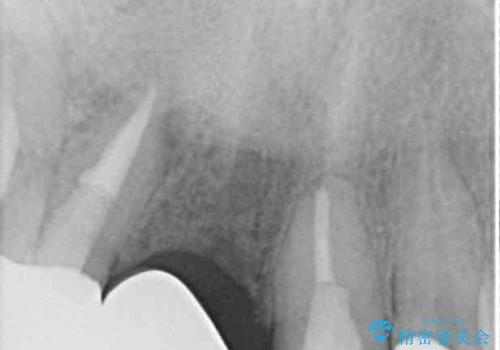

検査したところ、右前歯は抜歯が必要であったので、ブリッジを新製することとしました。

1歯は根管治療を行うことが必要と判断されたため、根管治療を実施することとしました。